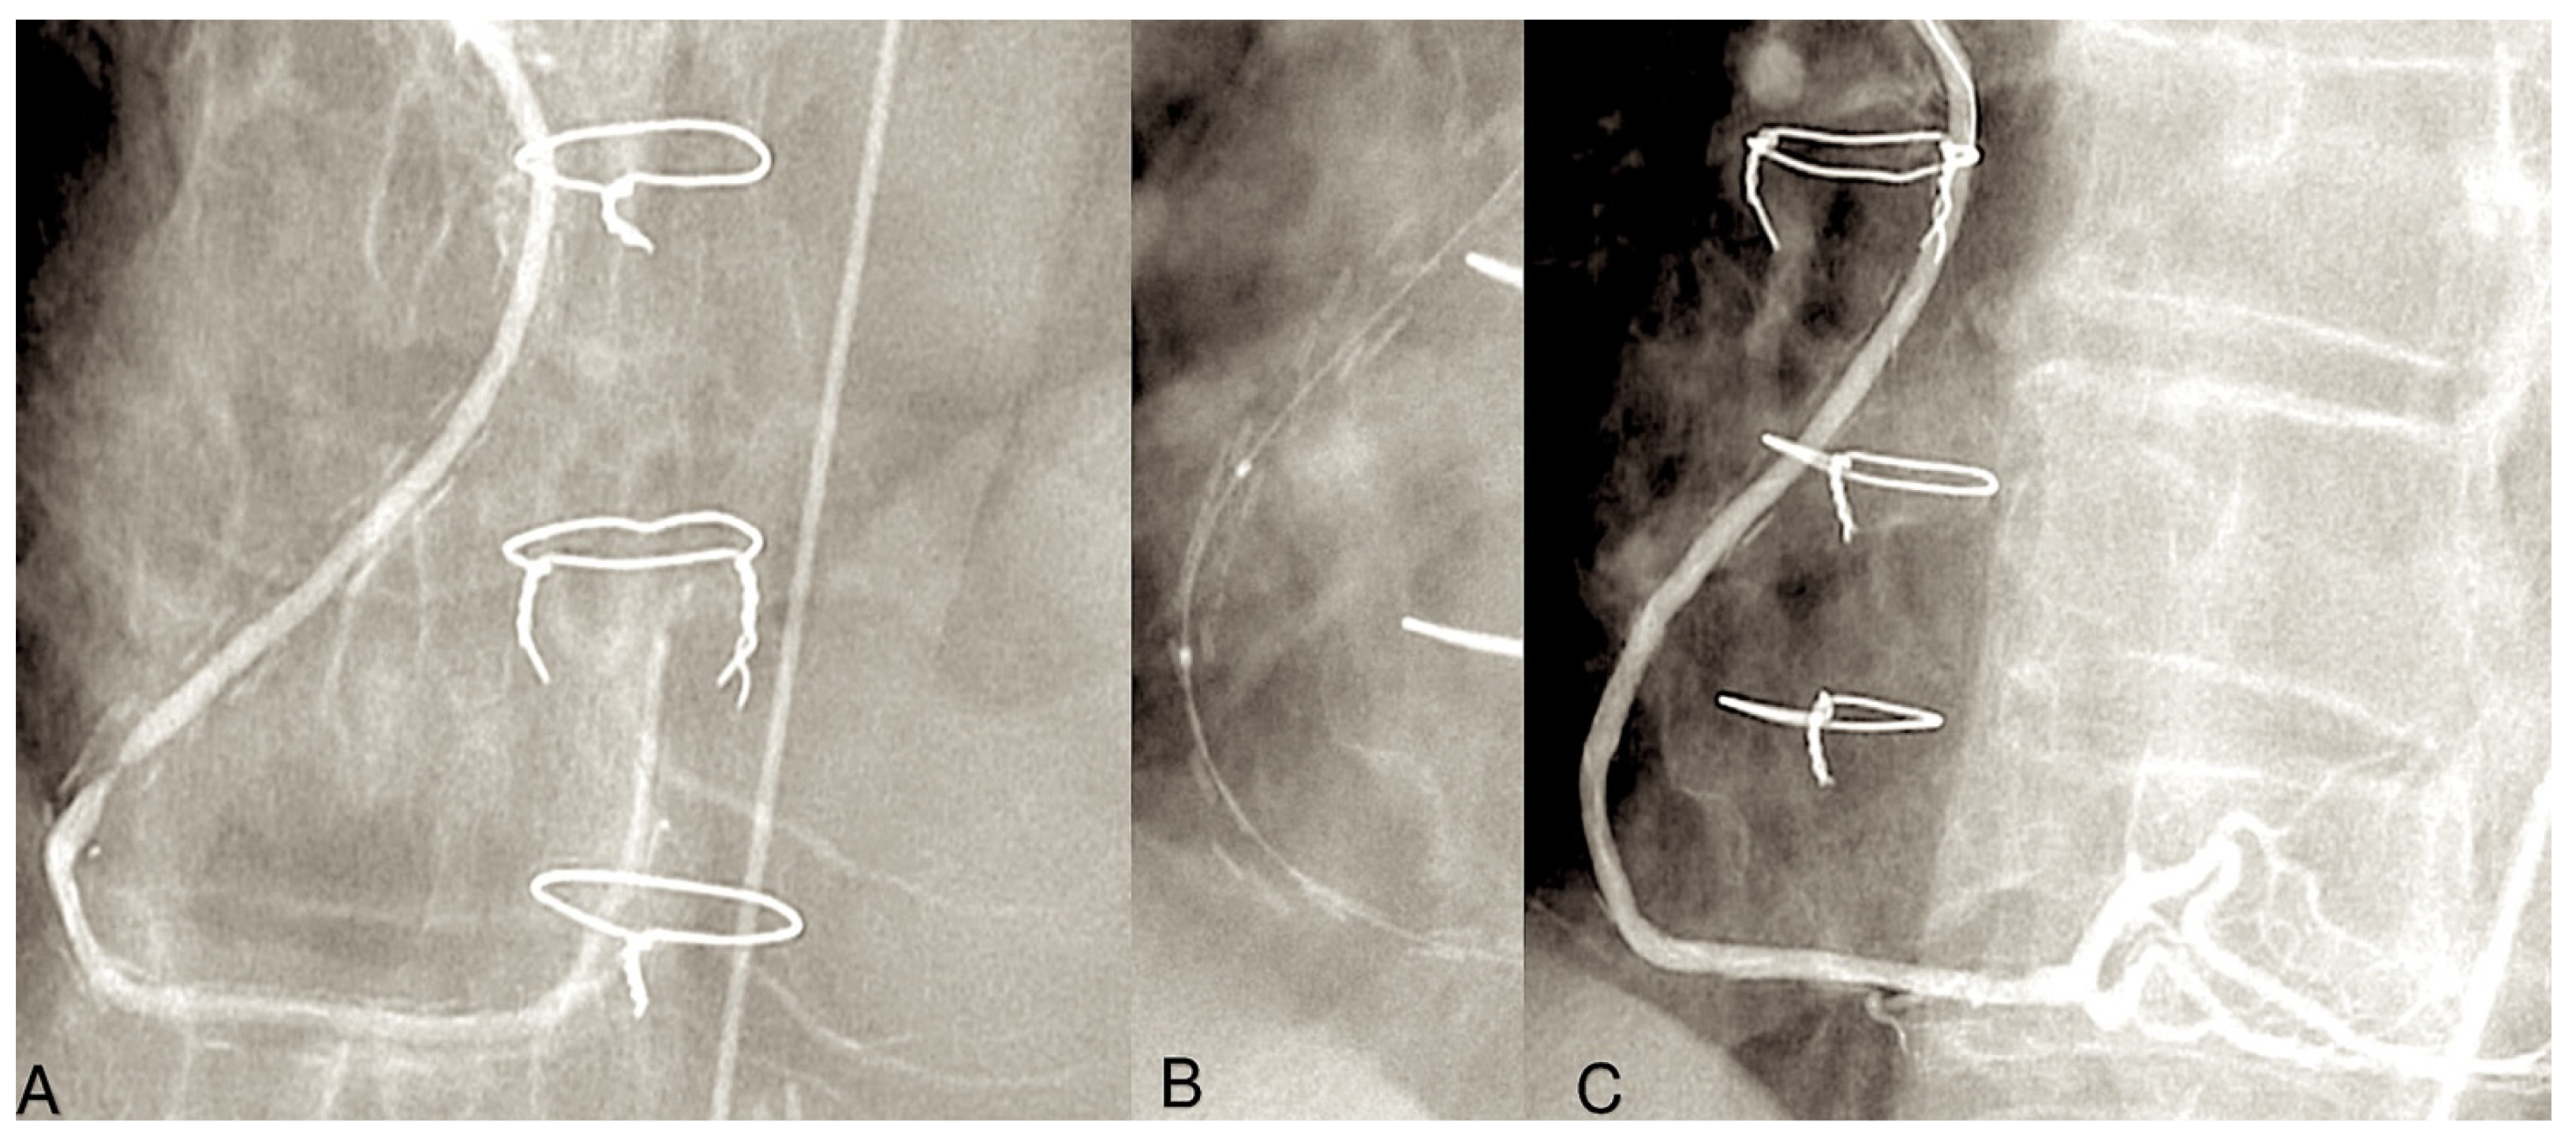

- Goube, P.; Hammoudi, N.; Pagny, J.Y.; Boutekadjirt, R.; Toledano, D.; Achouh, P.; Acar, C. Radial artery graft stenosis treated by percutaneous intervention. Eur. J. Cardiothorac. Surg. 2010, 37, 697–703. [Google Scholar] [CrossRef] [PubMed]